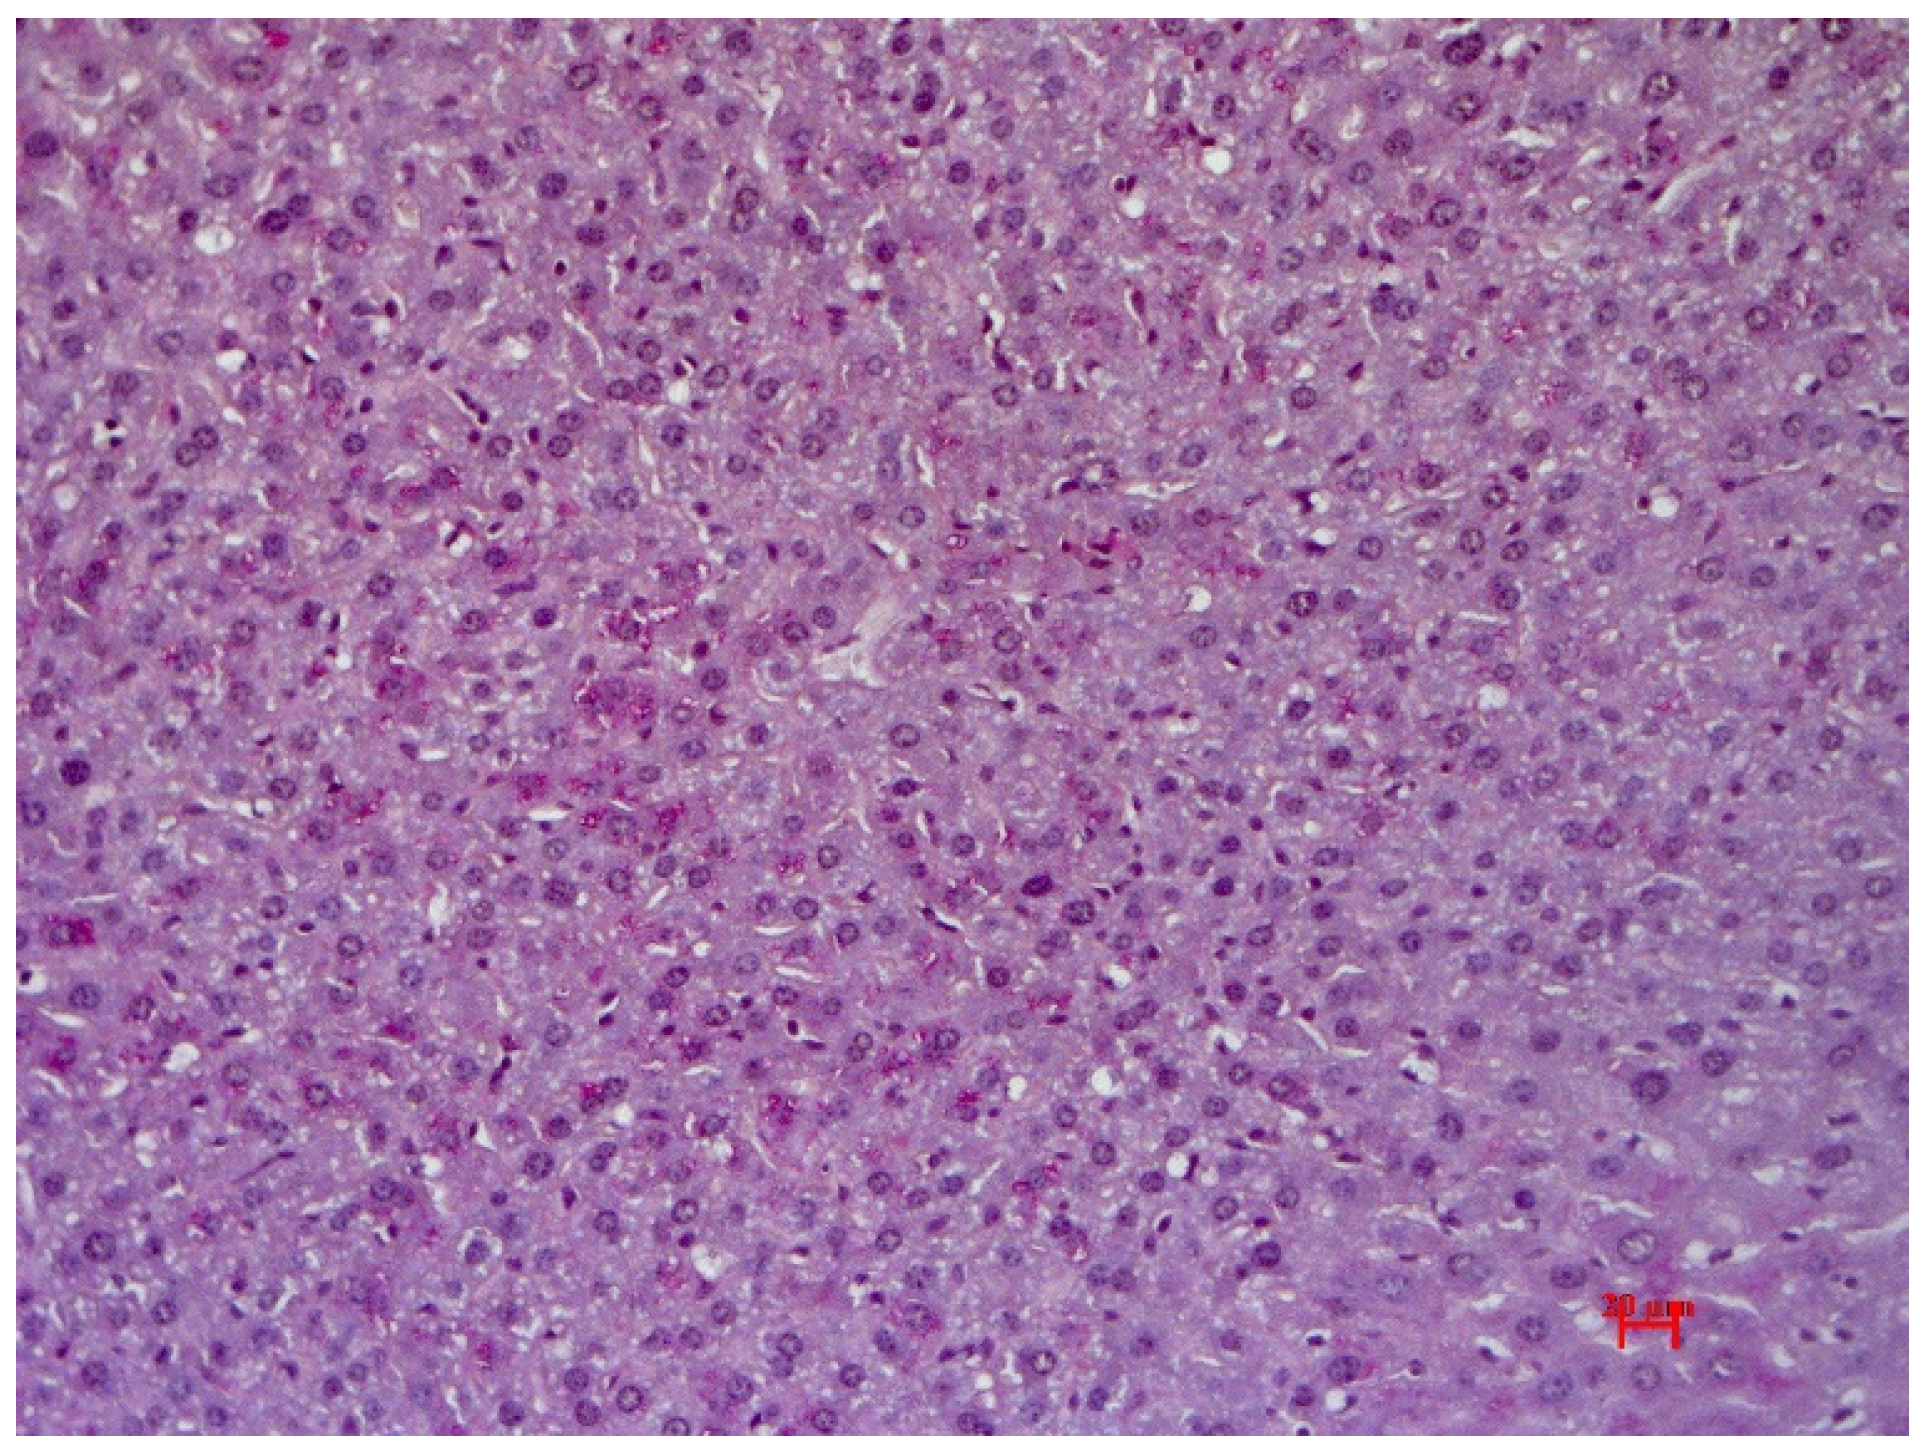

Animals in the control group showed preserved liver architectonics, bile capillary structure, veins and arteries; all were unchanged in mice of the control group. Moreover, no signs of pathological infiltration, dystrophy or fibrosis were found. Uneven glycogen distribution in the form of dust-like granularity was observed during Periodic acid–Schiff staining (PAS staining) (Figure 8).

Figure 8.

The liver of control mice without pathological changes. Glycogen in single hepatocytes. Staining with PAS hematoxylin orange G, ×200.